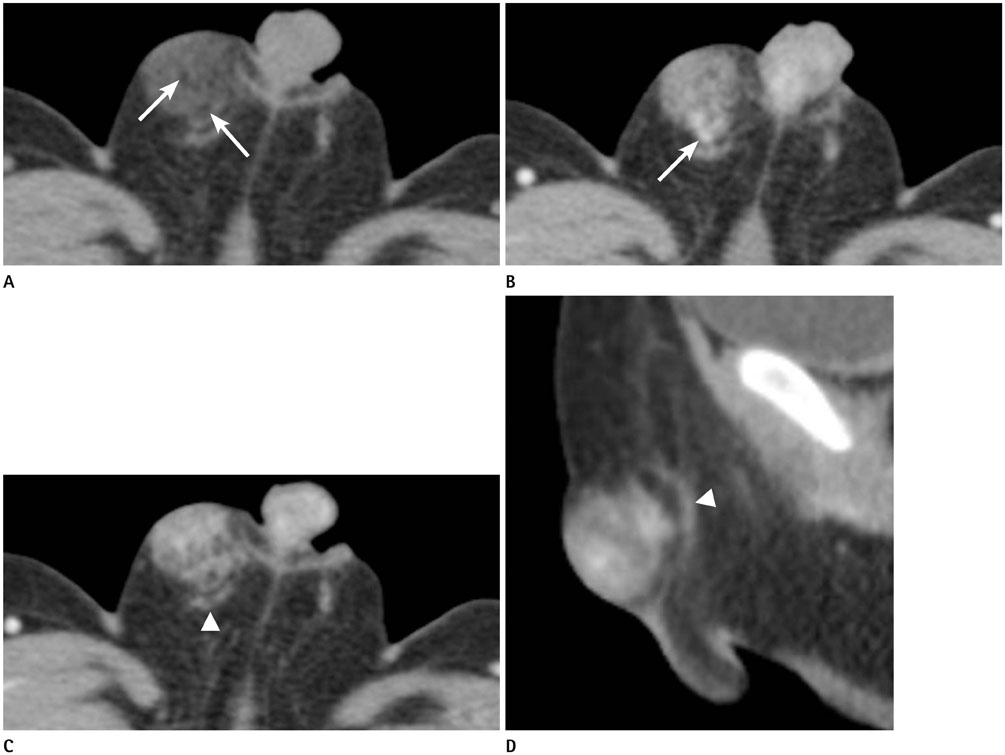

Fibrous Hamartoma of Infancy in the Scrotum: A Case Report

- Fibrous hamartoma of infancy (FHI) is a rare, benign subcutaneous tumor occurring mainly before the age of 2 years. The most commonly reported locations of FHI are the extremities such as the shoulder or axilla. However, FHI arising in the genital area is extremely rare and has not been reported with correlated radiologic findings. In this case report, we present a case of 5-month-old male child diagnosed with FHI in the scrotum, with a focus on the correlation between the radiologic and pathologic findings.